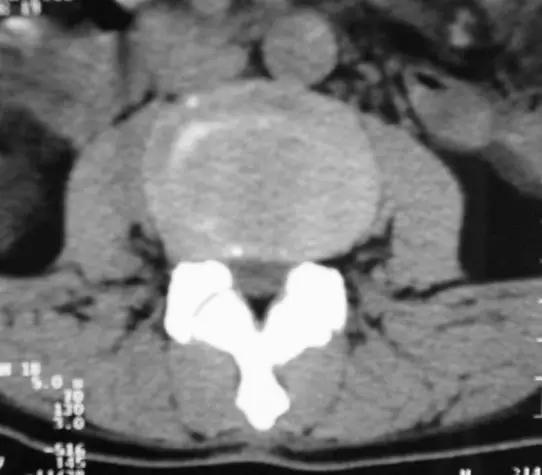

椎间盘突出的CT表现

直接征象:A、椎间盘后缘向椎管内局限性突出,密度与相应椎间盘一致,形态不一。B、突出的椎间盘可有大小、形态不一的钙化,多与椎间盘相连;C、椎管内硬膜外可见髓核游离碎片,密度高于硬膜囊;D、许莫结节表现为椎体上(下)缘边缘清楚的隐窝状压迹,多位于椎体中后1/3交界部,常上下对称出现。其中心密度低,为突出的髓核及软骨板,外周为反应性骨硬化带。

间接征象:A、硬膜外脂肪间隙变窄、移位、或消失。B、硬膜囊前缘或侧方及神经根受压移位。C、周围骨结构改变,突出髓核周围骨质硬化。

椎间盘膨出

轻度膨出时表现为椎间盘后缘正常肾形凹陷消失,圆隆饱满。

重度时弥漫膨出的间盘边缘明显向四周均匀一致增宽,超出上下椎体边缘,但椎间盘仍然对称,没有局部突出,外形保持椭圆形,可伴真空变性。严重时可造成硬膜囊受压狭窄,马尾神经受压。

椎间盘膨出伴右后突出

椎间盘脱出伴髓核游离

椎间盘脱出